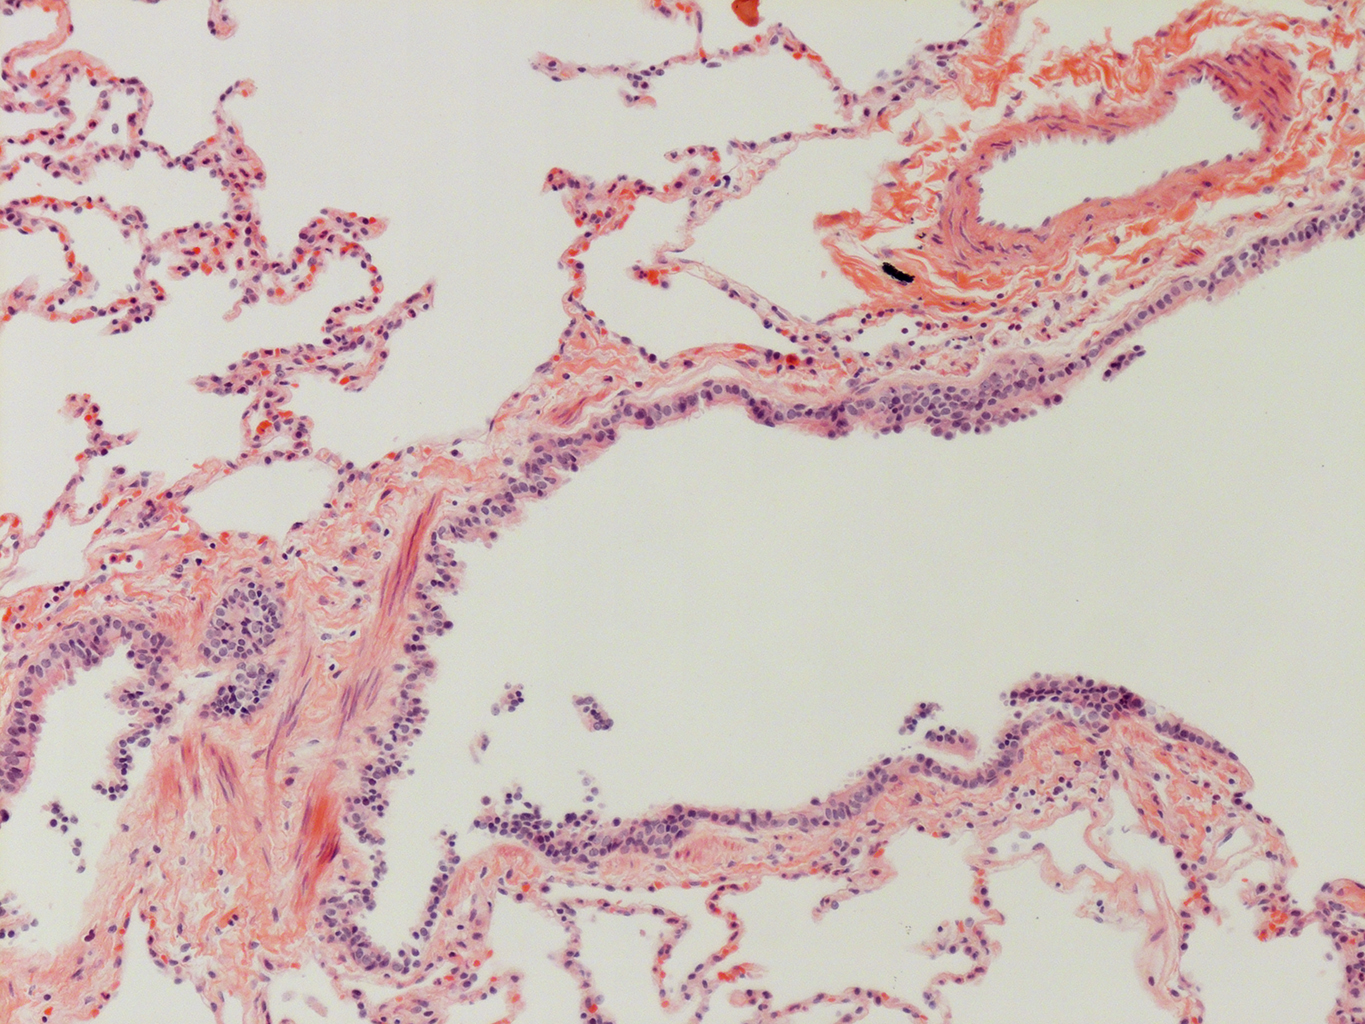

Donor tissue kindly provided by Dr. Scott Randell, University of North Carolina

Tissue Used:

LMHA-15-UNC-2017-12-19_D0037L.05HP_3_48

Gender: Male

Age:Â 43 Year Old

Race: Hispanic

Non-Smoker